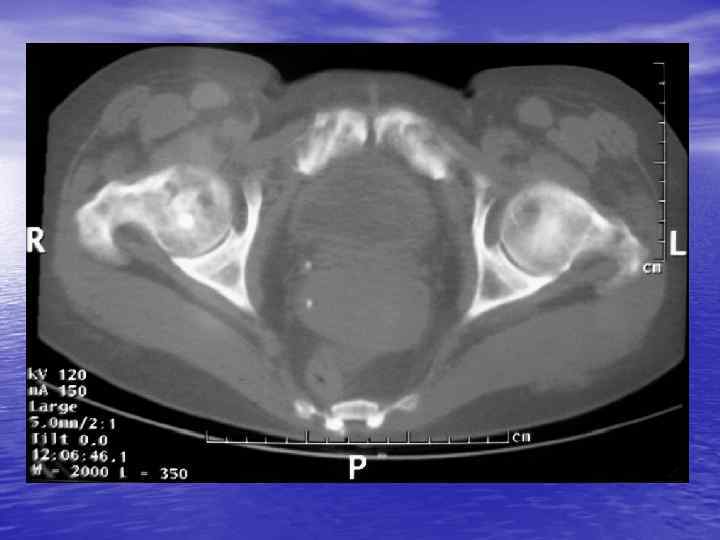

Денситометрический анализ Определение основных видов патологических образований: - обызвествленных - мягкотканных - жидкостных - жиросодержащих - воздухсодержащих

Денситометрия